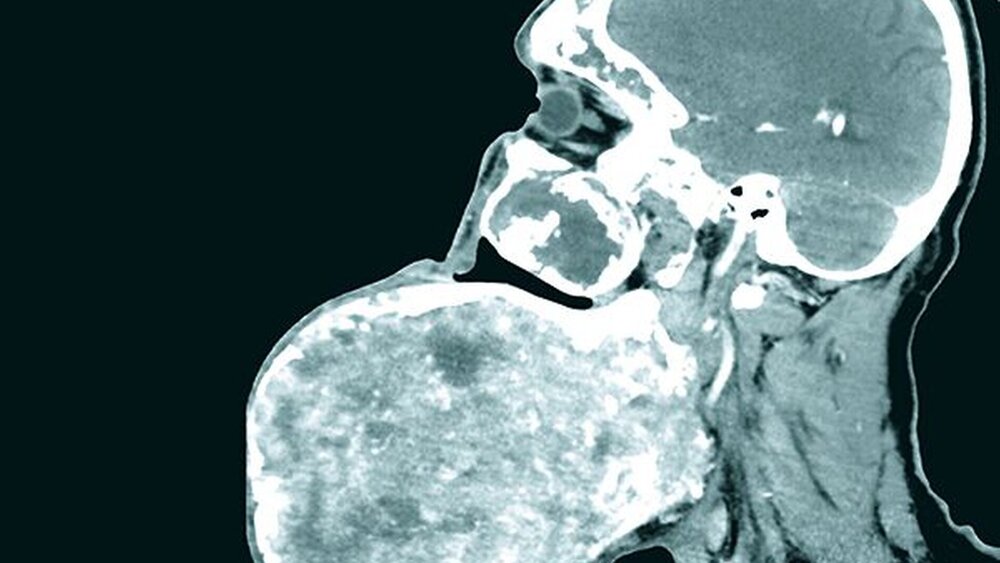

Klinisch zeigte sich eine circa 30 cm x 28 cm x 15 cm große, knochenharte und den Unterkiefer zu drei Vierteln umgreifende Raumforderung ohne Vincent-Symptomatik (Abbildung 1). In der Computertomografie zeigte sich eine inhomogene, blasige und hypodense Raumforderung mit Milchglasanteilen (Abbildung 2). Geplant wurde eine Abtragung der Veränderung mit Rekonturierung des Unterkiefers unter Verwendung eines statistischen 3-D-Formmodells, mit dessen Hilfe die ursprüngliche Form des Unterkiefers ermittelt wurde (Abbildung 3a). Im CAD/CAM-Verfahren wurden vier Resektionsschablonen hergestellt, um die geplante Osteotomie intraoperativ umzusetzen (Abbildung 3b).